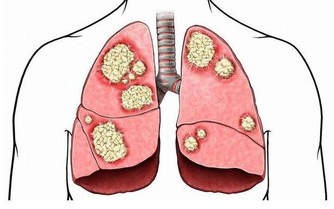

當患者未能及時接受治療時,癌細胞會擴散到身體的其他組織和器官,例如肝臟。

而當癌細胞進一步擴散,病情逐漸惡化時,會影響到消化系統以外的部分。

嚴重時還會導致貧血和呼吸困難,皮膚和眼白也會開始泛黃。